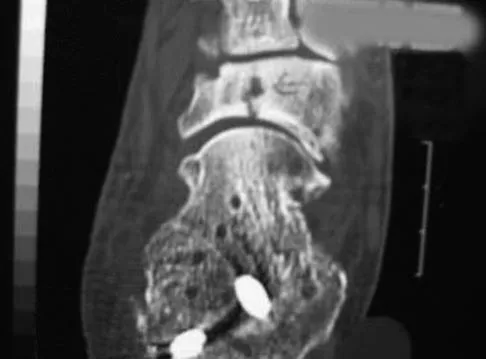

A 64-year-old man with a history of diabetes mellitus underwent open reduction and internal fixation of a displaced ankle fracture 8 weeks ago. Examination now reveals recent onset erythema, warmth, and swelling of the midfoot. Radiographs are shown in Figures 23a through 23d. What is the most likely reason for the swelling of the foot?